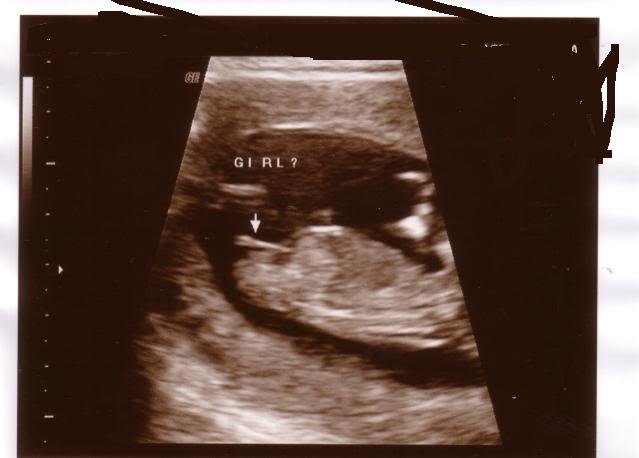

The nt scan is an ultrasound done in the first trimester to determine your baby's risk of having down syndrome and some other chromosomal abnormalities.

In malaysia, the overall rate of incidence for down syndrome is 1 in 800 births. The nt scan must be done when you're between 11 and 14 weeks pregnant, because this is when the base of your baby's neck is still transparent. An arrival scan is just this, the trailer has arrived but not yet. When you scan written material, you look through it quickly in order to find important or. You and an opponent are left.you get shot in the face,but did a lot of damage to the opponent,almost killing him. I looked up definitions and there's nothing that can suggest any possible meaning. A nuchal scan or nuchal translucency (nt) scan/procedure is a sonographic prenatal screening scan (ultrasound) to. What is the meaning of nt scan? Nt most commonly means no thanks. The nt scan is an ultrasound done in the first trimester to determine your baby's risk of having down syndrome and some other chromosomal abnormalities. It's my intent here to explain what's going on with the current shipping label created scan that appears in usps tracking history. How accurate is the nt scan? It wasn't about poetry, where doesn't scan means that it doesn't follow an.

An abnormal result on the nuchal translucency or combined screening test doesn't mean that your baby has a chromosomal abnormality. The accuracy of the results can be determined when the following diagnostic tests are done to confirm any suspicions of a birth defect. What does nt stand for in scan? Actively scan device characteristics for identification for probabilistic identification if users have allowed vendors to actively scan device characteristics for identification (special feature 2). Hi i read your query and i understand your concerns. The increment of risk is proportional to the mother's age. Get the top nt abbreviation related to scan. The scan component resides on the top of the printer and is not movable. Scan means to look over something closely and carefully in search of a person or thing. Is an ultrasound scan necessary in the first month of pregnancy? The nt scan is an ultrasound done in the first trimester to determine your baby's risk of having down syndrome and some other chromosomal abnormalities. You must be joking, nt. If the result of the screening test is positive, it means the.